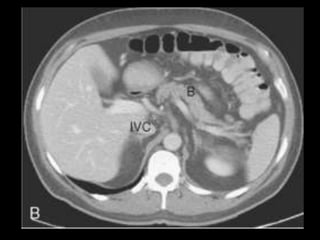

Pseudocistos-TC

Coleção líquida redonda ou oval, com uma parede

fina ou espessa, que apresenta intensificação pelo

contraste;

RM: lesão uniloculada bem definida, hipointensa

em T1 e hiperintensa em T2;

Bolhas de gás: infecção, fístula ou à cistostomia

interna;

Hemorragia aguda dentro do cisto: hiperdensa

Estenose ou oclusão venosa, com formação de

varizes ou pseudoaneurismas.

Pseudocistos- complicações

Obstrução biliar

Obstrução do TGI

Invasão do baço ou do fígado

Ruptura no peritônio

Pseudocistos < 5 cm: podem se resolver

espontaneamente e devem ser monitorados

Pseudocistos > 5 cm, em expansão, causando

fortes dores ou obstruindo: drenagem